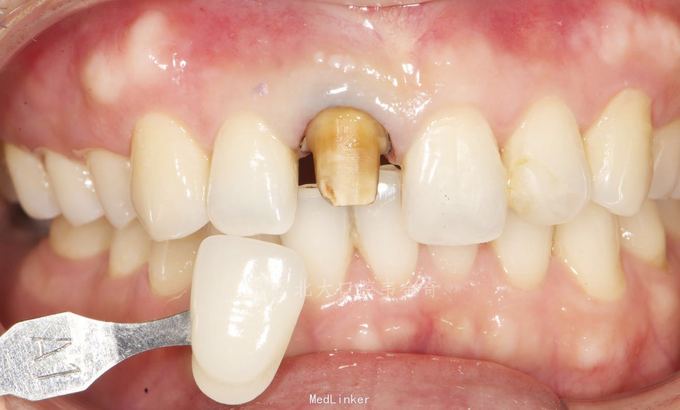

诊断:11牙体缺损,牙冠变色。 处理:建议桩核冠修复。常规操作完成纤维桩树脂核,以及铸瓷冠修复。